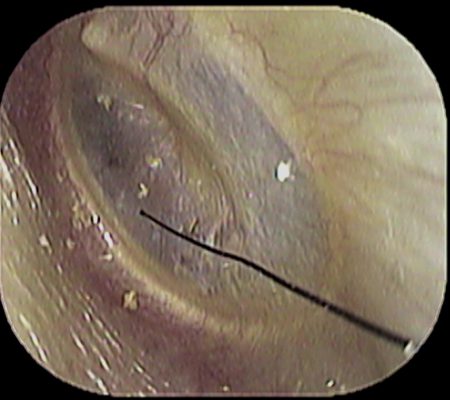

岩倉市の「いのうえ耳鼻咽喉科」 院長の井上です。

先日のことです。

「耳

がガサガサする」とのことで当院受診された患者さんがおられました。

患者さんは「虫🕷でも入っていたら・・」と心配の様子

早速 耳

を診てみると

耳垢もありましたが、髪の毛がありました。

その先を追っていくと↓

奥まで入っており

先端が、鼓膜に触れていました。

これがガサガサの原因です。

除去し、症状は無事 消失しました。

耳症状が気になる方は、耳鼻咽喉科の受診をお勧めいたします